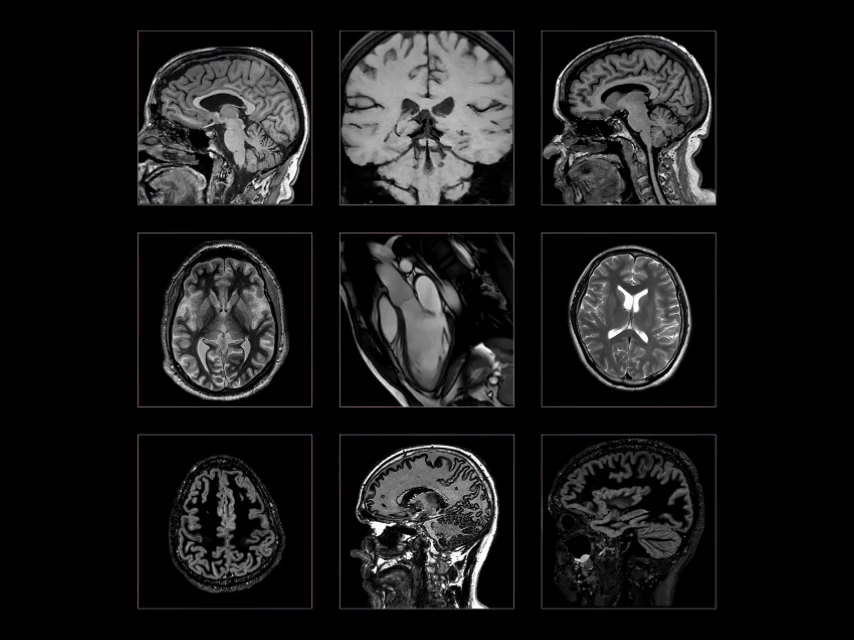

Công nghệ chẩn đoán hình ảnh hiện đại không sử dụng tia bức xạ, MRI đóng vai trò bổ trợ quan trọng cho CT, X-quang và siêu âm, hỗ trợ phát hiện những bất thường ở não, tim, mạch máu, cơ quan nội tạng…

• Chẩn đoán hình ảnh: CT scan toàn thân (cổ, ngực, bụng, chậu); MRI sọ não.